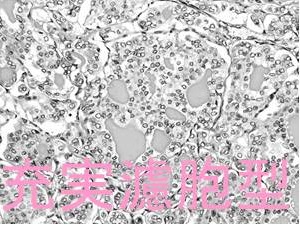

小児甲状腺乳頭癌充実亜型[充実型乳頭癌](Solid variant of papillary thyroid carcinoma:SVPTC)は、(乳頭構造・濾胞構造を取らず)充実性に増殖する成分が全体の50%以上を占める甲状腺乳頭癌亜型です。核には甲状腺乳頭癌の特徴的所見を認めます。

ヨード(ヨウ素)過剰地域の日本で、小児甲状腺乳頭癌充実亜型[充実型乳頭癌](SVPTC)はほとんどなく(乳頭癌全体の1-3%)、近いものでも濾胞構造が混在する充実濾胞型です。

甲状腺乳頭癌充実亜型の細胞診、組織診